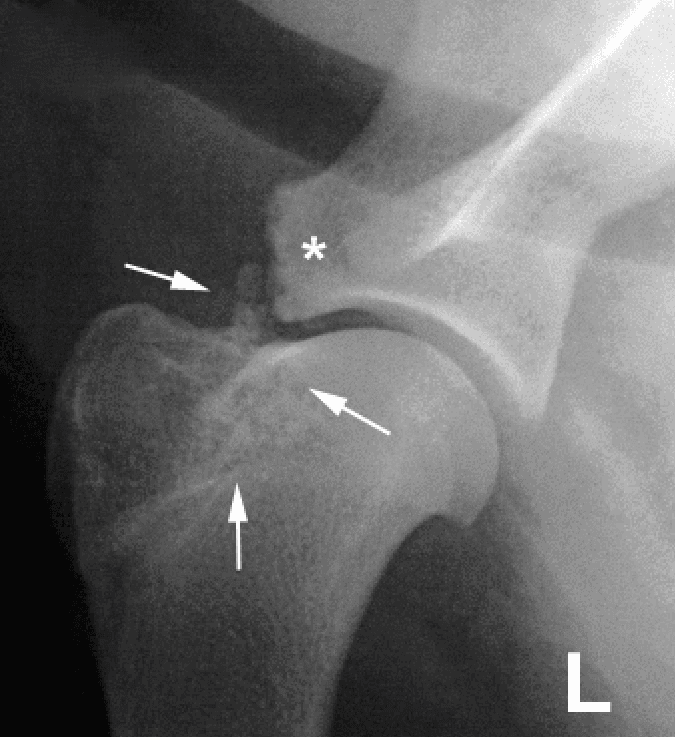

Biceps Tendinopathy involves irritation or damage to the biceps tendon which affects the tendon’s ability to glide through the biceps groove. This can occur either from sources within the joint, like wear and tear damage to the biceps tendon itself or irritation from a migrating OCD lesion. Alternatively, impingement of the tendon can occur outside of the joint from sources like a mineralized supraspinatus tendon.

Diagnosis is generally made on examination with pain elicited on palpation of the biceps tendon when the elbow is extended and shoulder flexed, which stretches out the tendon.

X-rays can show mineralization of the tendon or where it attaches to the scapula. Advanced imaging with ultrasound, CT scan, or MRI can be performed but are not generally necessary.